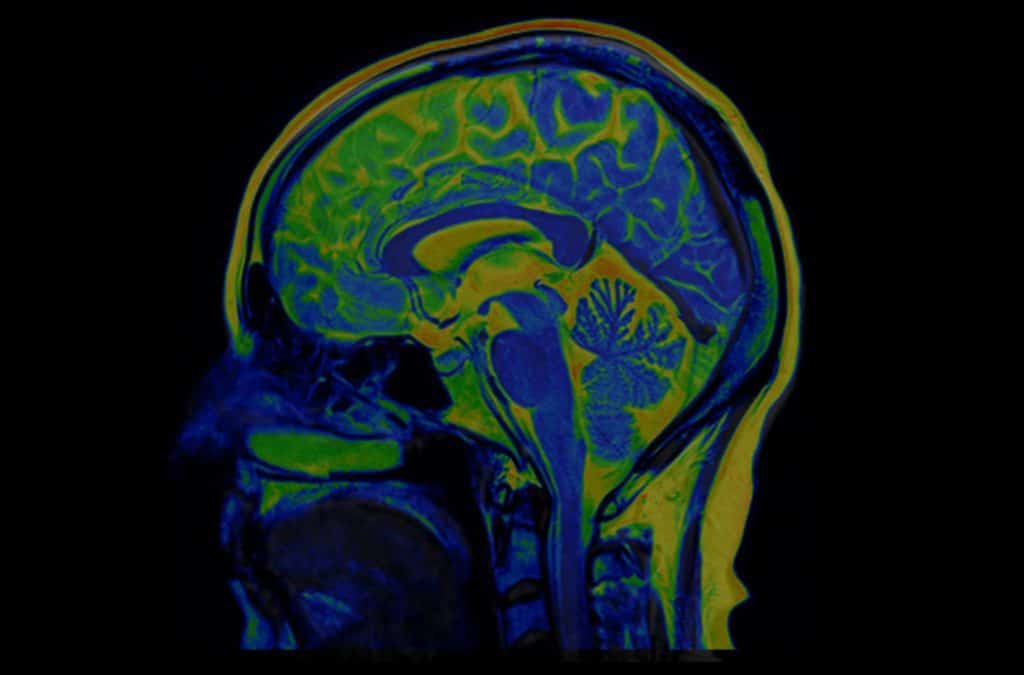

SPECT ili jednofotonska emisijska kompjutorizirana tomografija je naziv za noviji dijagnostički test koji omogućava detaljniju analizu organa, kostiju te tkiva pacijenta. Riječ je o vrsti nuklearnog snimanja, što znači da se primjenjuje radioaktivna tvar, te posebna kamera za snimanje i stvaranje 3D slika. Dok snimanje sa X zrakama omogućuje pokazivanje unutrašnjosti tijela, SPECT se bazira na proizvodnji slika koje će pokazati funkciju organa, kostiju ili tkiva. U primjeru, jednofotonska kompjutorizirana tomografija prikazuje protok krvi u srce, koji dio mozga ja aktivan, koji dijelovi tijela su zahvaćeni rakom i u kojem omjeru.

Jednofotonska emisijska kompjutorizirana tomografija se najčešće koristi kada postoji sumnja na probleme s mozgom, srcem, kostima. Poremećaji mozga - Ovdje će navedeni test stvoriti detaljnu 3D mapu aktivnosti samog mozga i protoka krvi u njemu, što daje do znanja u kojem djelu mozga je problem. Pokazuje: Začepljene krvne žile u mozgu, napade koji se nalaze u određenim dijelovima mozga (Alzheimerova i Parkinsonova bolest, epilepsija, razvoj demencije). Nekada se koristi i radi utvrđivanja traume glave.